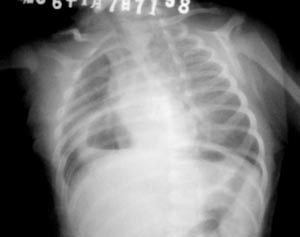

出生50天,倒奶5天,3天未解大便,无发热、咳嗽

右下肺内带较大含气囊样阴影,其内见液平,囊壁尚清晰。

右下肺内带较大含气囊样阴影,其内见液平,囊壁较厚尚清晰。可见胃泡影。肠管内气体影少见。

出生50天,倒奶5天,3天未解大便,无发热、咳嗽。考虑:1)消化道重复畸形可能大;2)先天性幽门肥厚。

病人体位略不正,膈上纵隔右胸腔内带可见一气囊影,下部示气液平面,囊壁较光整,与肺界面清晰,其左下角与胃泡关系密切,胃泡内气体较少,支持膈疝。

右侧肋骨上抬,右侧胸腔见空泡内有液平,其壁似与下方肠管连续,考虑膈疝吧。